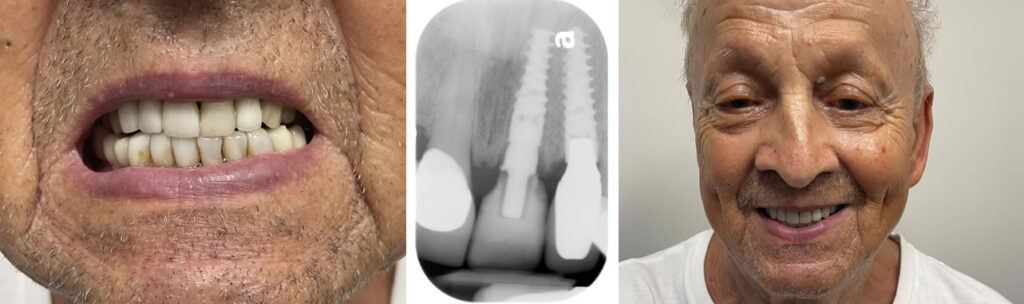

Broken Front Tooth Emergency Treatment

Implant and Temporary Crown within One Hour

Our clinic provides urgent assessment and dental implant treatment to replace a damaged front tooth with a secure, natural-looking solution.

Emergency exams booked within 2 hours. Emergency Implant treatment scheduled within 24-48 hours from exam. We offer a FREE Consultation and FREE Low Radiation X-Rays. A broken or knocked-out front tooth is more than a dental problem. It’s an immediate aesthetic and functional emergency. Our clinic provides urgent assessment and dental implant treatment to replace a damaged front tooth with a secure, natural-looking solution. Using premium Nobel Biocare implant systems, we restore your smile with precision shade-matching and gum line aesthetics so your new tooth blends seamlessly with the rest of your smile.

In many cases, we can place the implant promptly after evaluation and provide a temporary tooth the same day, so you never have to leave with a visible gap. Dental implants also preserve the jawbone and prevent neighbouring teeth from shifting and making them the most stable, long-term replacement for a broken front tooth.